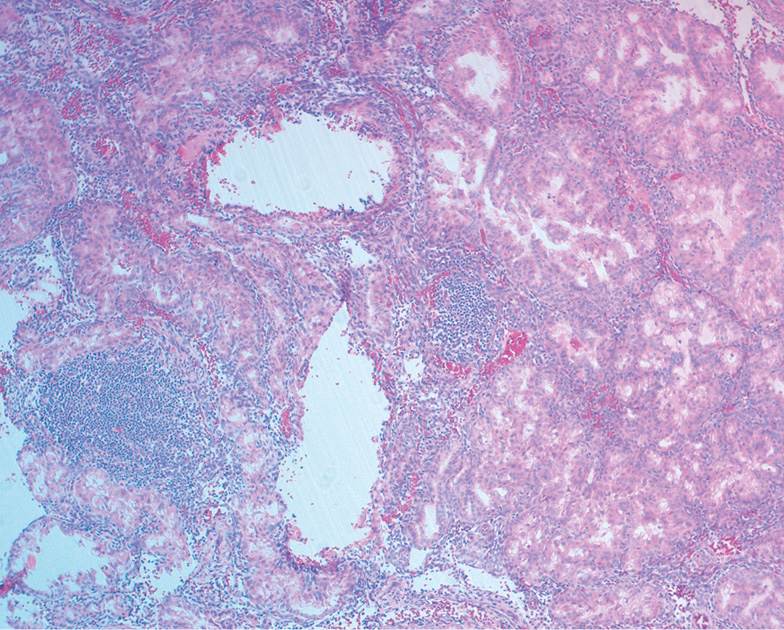

染色体绒毛膜异常组的子宫内膜在大多数情况下(88.13%)也有中度至重度淋巴细胞和巨噬细胞浸润的特征(表3)。与整倍体组相比,微脓肿型白细胞聚集的频率几乎增加了3倍(p<0.001)(图3)。 正常核型组的特点是缺乏蜕膜转化约三分之一的病例,有轻度至中度的炎症浸润(见表3)。

白细胞按微脓肿类型积聚 | 72 | 42.60 | 16 | 15.38 | <0.001 |

无论怀孕的时间长短和宫腔中不可存活的孕囊持续时间,直至手术干预时刻,都观察到流产胎儿中所描述的炎症变化。